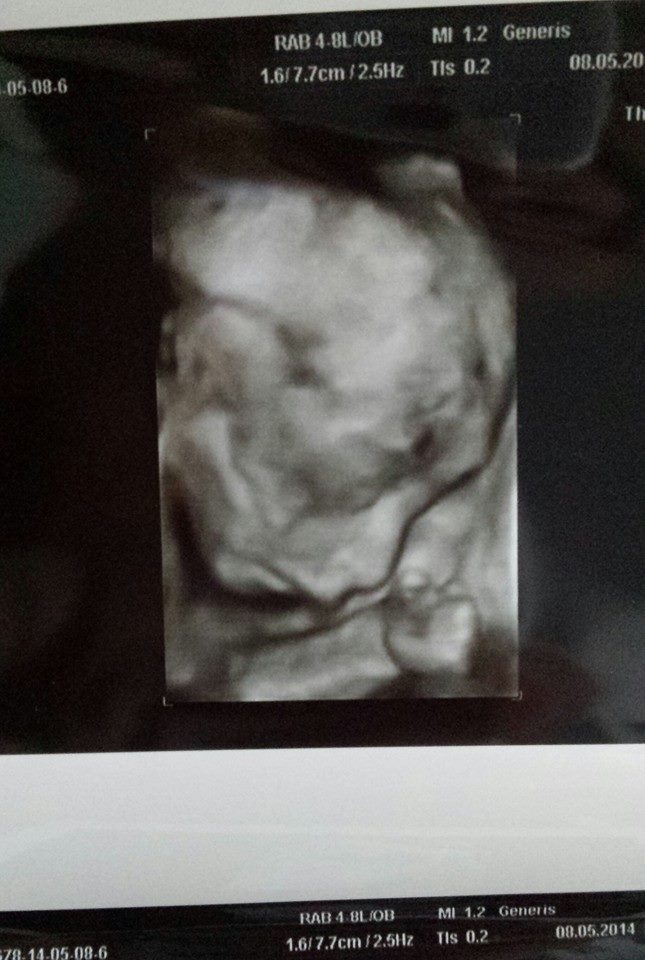

Frumoasa blondă a postat recent pe pagina personală de Facebook o fotografie incredibilă. Iubita lui Nicolae Guţă a pus ecografia fetiţei lor, în care se pot observa toate trăsăturile feţei: nasul, gura şi ochii. Mai mult, mânuţa mică şi strânsă îţi smulge lacrimi de emoţie. "Prinţesa mea Anais", scrie Beyonce de România pe contul de socializare.